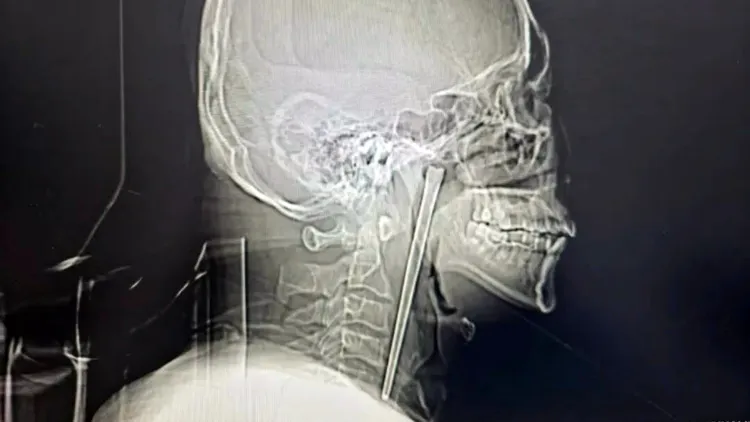

據中國《瀟湘晨報》報導,46歲的王男在8年前誤吞筷子後,就感覺咽喉陣陣疼痛,他隨即到醫院就診,醫師告知必須切開側頸部才能把筷子取出,他對手術安全性存疑,於是決定放棄治療,讓這根筷子待在自己咽部。

王男表示,此後8年來,雖然偶爾會出現輕微不適,但他覺得尚能忍受,直到近來突然感覺咽部明顯疼痛,吞咽時更是劇痛,還有強烈的異物感,所以才再次到醫院檢查。

醫師檢查後發現,這根筷子鄰近的咽部黏膜沒有出現明顯破潰、出血及化膿等情況,聲帶活動正常,喉腔結構也沒有受到壓迫移位。於是為他進行口腔異物微創手術,不用頸部開刀,讓王男點頭同意接受手術,最終成功取出這根待在體內8年的筷子。

王男近來因為患部疼痛加劇就醫,終於通過手術取出在咽部卡了8年的筷子。翻攝自微博